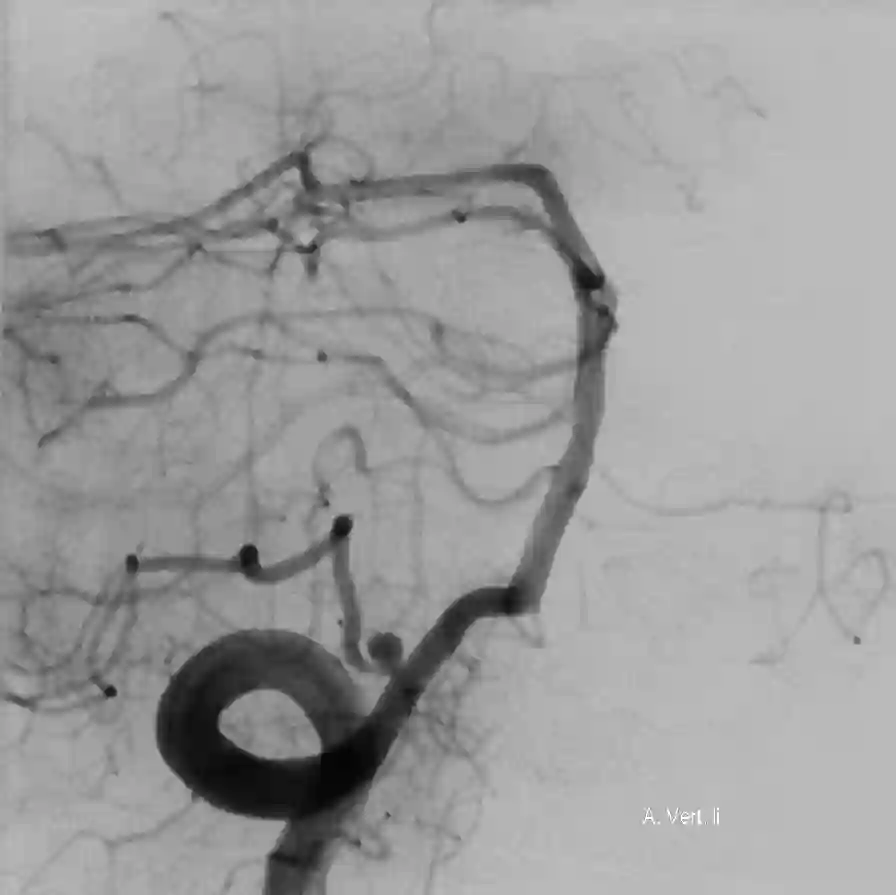

Die PICA entspringt in der Regel direkt aus der Arteria vertebralis. Üblicherweise entspringt die PICA hierbei ca. 10 mm distal zu jenem Punkt, wo die Arteria vertebralis intradural wird und etwa 15 mm proximal zur vertebrobasilären Verbindung[^1]. In etwa 5-8 % der Fälle hat die PICA einen extraduralen Ursprung[^1]. Eine weitere anatomische Variante ist die AICA-PICA, hierbei entspringt die PICA aus der Arteria basilaris an gleicher Stelle wie die AICA. Die PICA zeigt angiographisch eine craniale- und caudale Schleife sowie den Choroidal Point. Die PICA kann in fünf verschiedene Segmente eingeteilt werden[^4]:

Tonsillomedullary: Bis zur tosillären midportion. Beinhaltet die kaudale Loop auf der Angiographie.

Telovelotonsillary (supratonsillar): Steigt in der tonsillomedullary fissure auf. Beinhaltet die kraniale Loop auf der Angiographie.

Abbildung